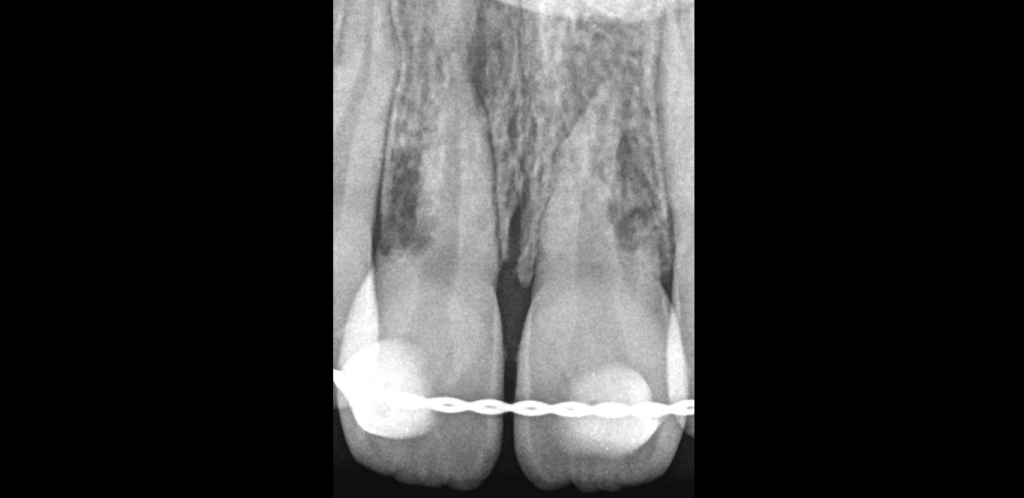

🔍 11 21

ATCD de traumatisme dentaire

Pulpe nécrosée, parodontite apicale symptomatique

Résorption latéro-radiculaire externe, inflammatoire